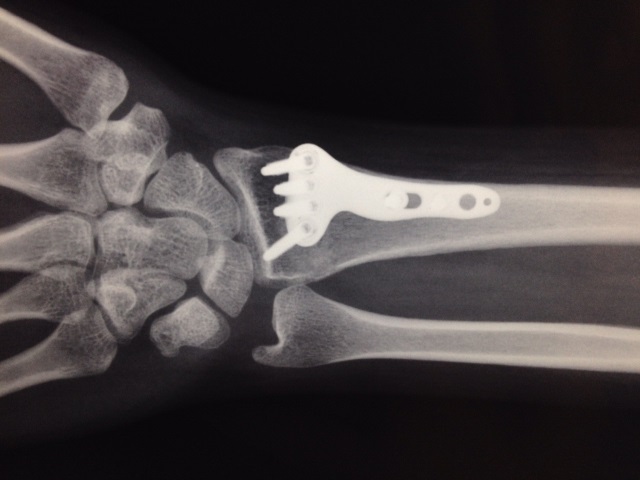

Radiografía final en la que se aprecia claramente el material implementado para fijar la fractura mediante un procedimiento realizado con técnicas de mínima invasión.